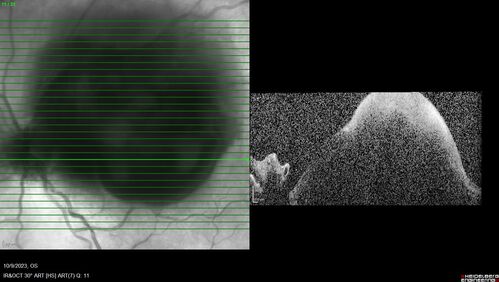

Ruptured Retinal Arterial Macroaneurysm - Submacular hemorrhage and BRAO

81 year old female with vision loss for a few days. Coumadin was high with INR at 3.1 VA 6/200